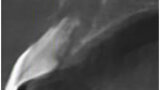

Ryc. 2_TK przedzabiegowe.